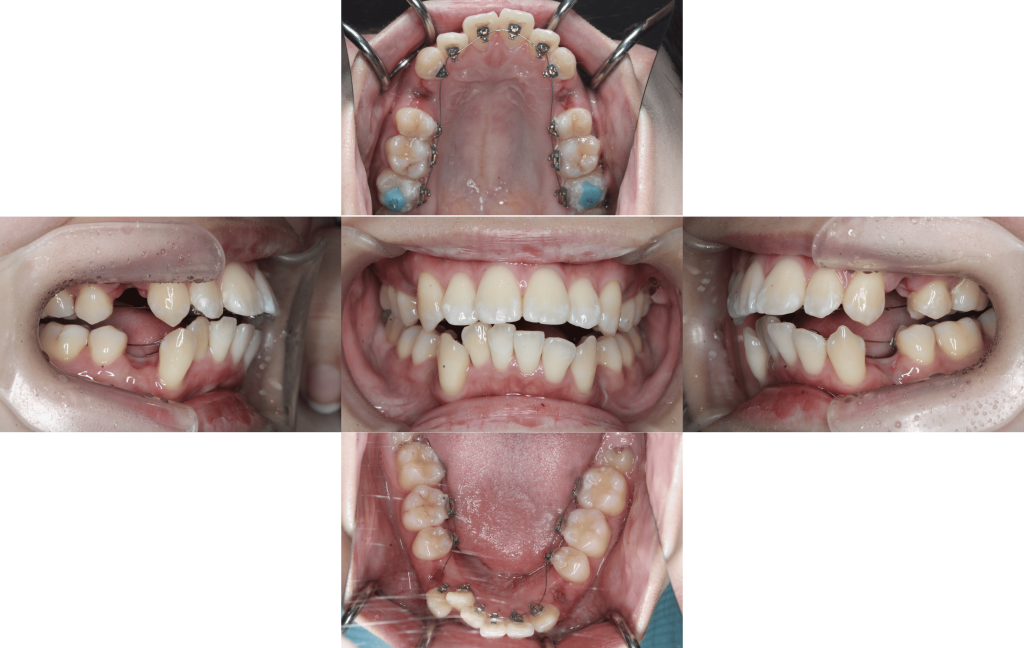

上下装置装着

約6か月経過